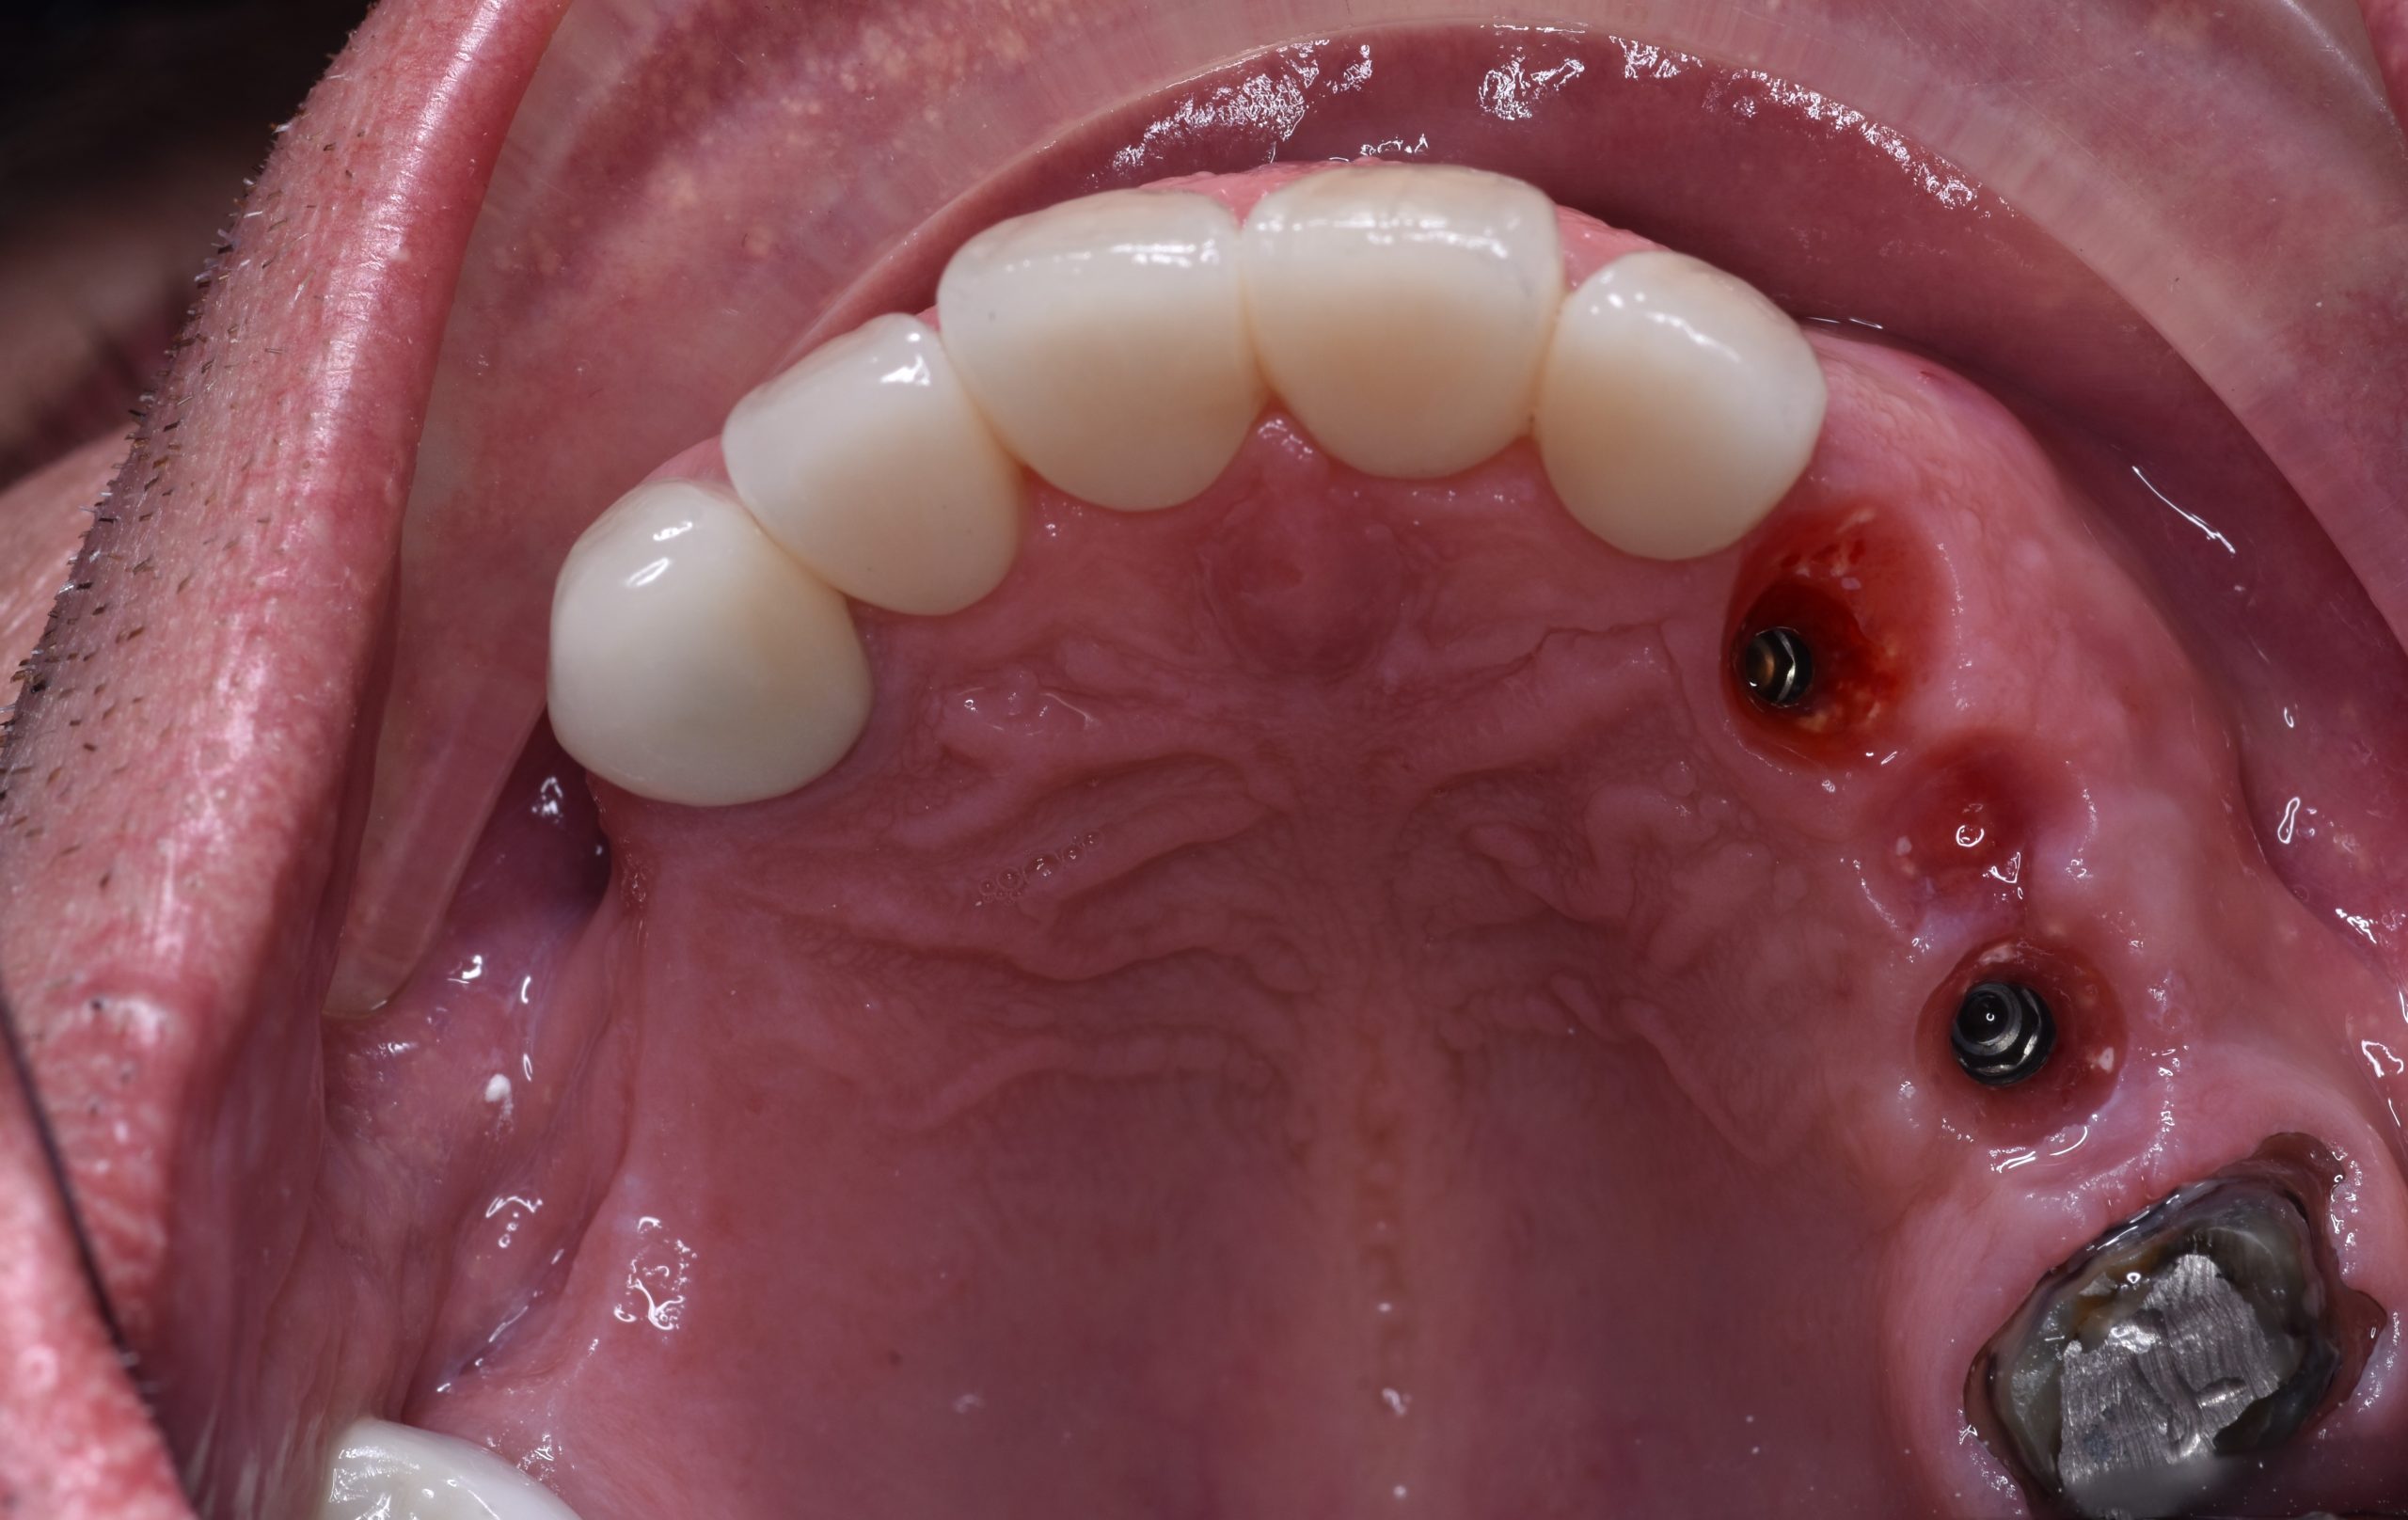

The first stage: remove teeth No.23,24 + place 2 implant body

The fouth stage: full mouth rehalibitation and finish the implant treatment.

Try-in the temporary crown